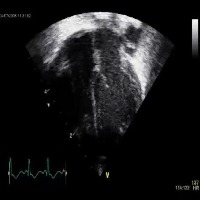

Medical Diagnostics: Medical professionals can employ the "echo_structures" model to improve patient care by facilitating the identification and analysis of cardiac structures via echocardiogram (ultrasound) images to provide a quicker and more accurate diagnosis of cardiovascular diseases and conditions.

Personal Health Monitoring: Integration of "echo_structures" model with mobile health apps and wearable devices (such as smartwatches) could allow for continuous and real-time monitoring of cardiac health, identifying abnormalities or potential concerns, and alerting users or healthcare providers when intervention may be needed.

Telemedicine Support: The "echo_structures" model could be incorporated into telemedicine platforms to assist remote medical professionals in diagnosing and treating cardiac conditions by allowing them to better understand patients' visual cardiac data and provide appropriate care from a distance.

Medical Research: Researchers in cardiology can utilize this model to efficiently process and analyze a large number of cardiac ultrasound images to study trends, monitor changes in heart structure or abnormalities, and support the development of novel medical approaches or innovative treatments for cardiovascular diseases.

Medical Training: The "echo_structures" model can serve as a valuable educational tool for medical students learning to read and interpret ultrasound images accurately. By automating the identification of cardiac structures, the model can provide immediate feedback, increasing students' learning efficiency and potentially improving overall diagnostic skills.